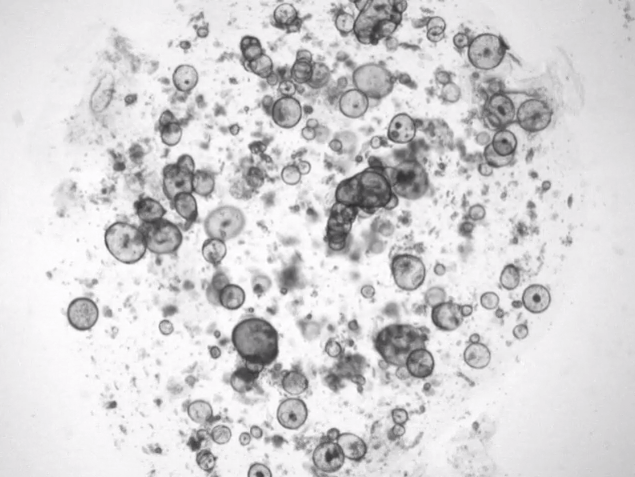

据外媒CNET报道,会“流泪”的无体人类泪腺听起来像是科幻电影里的东西。但来自Hubrecht研究所和UMC Utrecht的研究人员利用干细胞在培养皿中生长出微小的泪腺,以模仿真实的东西。他们希望这些所谓的有机体可以作为研究人类泪腺细胞如何产生眼泪的模型。他们的最终目标是:更好地理解和治疗干眼症或自身免疫性疾病干燥综合征以及泪腺癌症等疾病。

有机体是在体外以3D悬浮液的形式,从少量干细胞最终繁殖形成类似真实器官的东西,如小脑、膀胱,或在本例中,位于上眼睑内的腺体。

泪腺是由几种细胞组成的。荷兰研究人员培育的实验室生长的腺体只由一种类型组成,并在化学刺激下“哭泣”,如去甲肾上腺素,一种神经递质,从我们的神经元向我们的泪腺发出信息。

荷兰研究人员承认他们的泪腺有局限性,因为它只是由腺体中发现的主要细胞类型之一组成。他们说,他们最终想从组成泪腺的更广泛的细胞中培育出一个完整的泪腺,从而对我们如何形成眼泪有更深刻的理解。